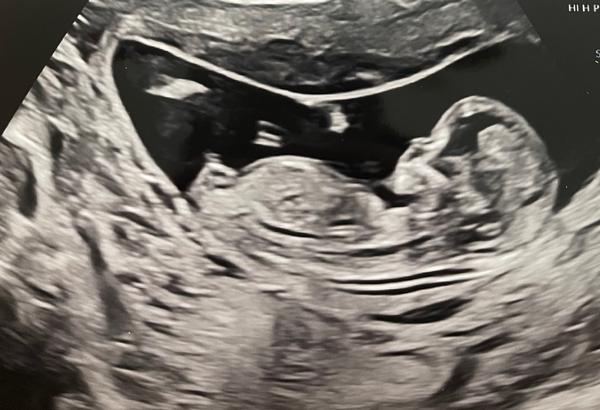

Tak co myslíte? Mám dvě fotky ze 13tt. Lékař mi svůj tip řekl - záměrně neprozrazuji! 🙂

Já to z tohoto nikdy nepoznám :D přijde mi, že hrbolek kouká dolů a je to holka...ale na druhém obrázku je nad tím zas něco..takže nevím, jsem marná. Já potřebuju ten pohled zespod 😀 ale tipla bych holku =)

Já bych podle první fotky řekla na 90% holka 🫣😁

Já tam vidím spis kluka.

@sishina podle 2 fotky si myslím chlapeček 😊. Tohle dcera na utz nemá 😅.

Tak je to zase 50 na 50 z fotky 12+0 to vypadalo na holku, dnes 12+4 na kluka. Tak jsme napnutý jako kšandy 🤣🤣🤣

Za mě kluk podle druhé fotky 🙂)